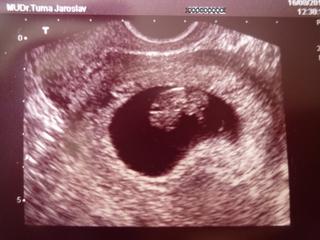

A ještě k tomu prcek vypadá jak krtek, viz foto 🙂))

@fifca krásná fazolka, super 😀

@fifca máte nádherný fotečky, já mám zatím jen takovou "fazolkovou" 🙂 , ale za týden už snad bude lepší.